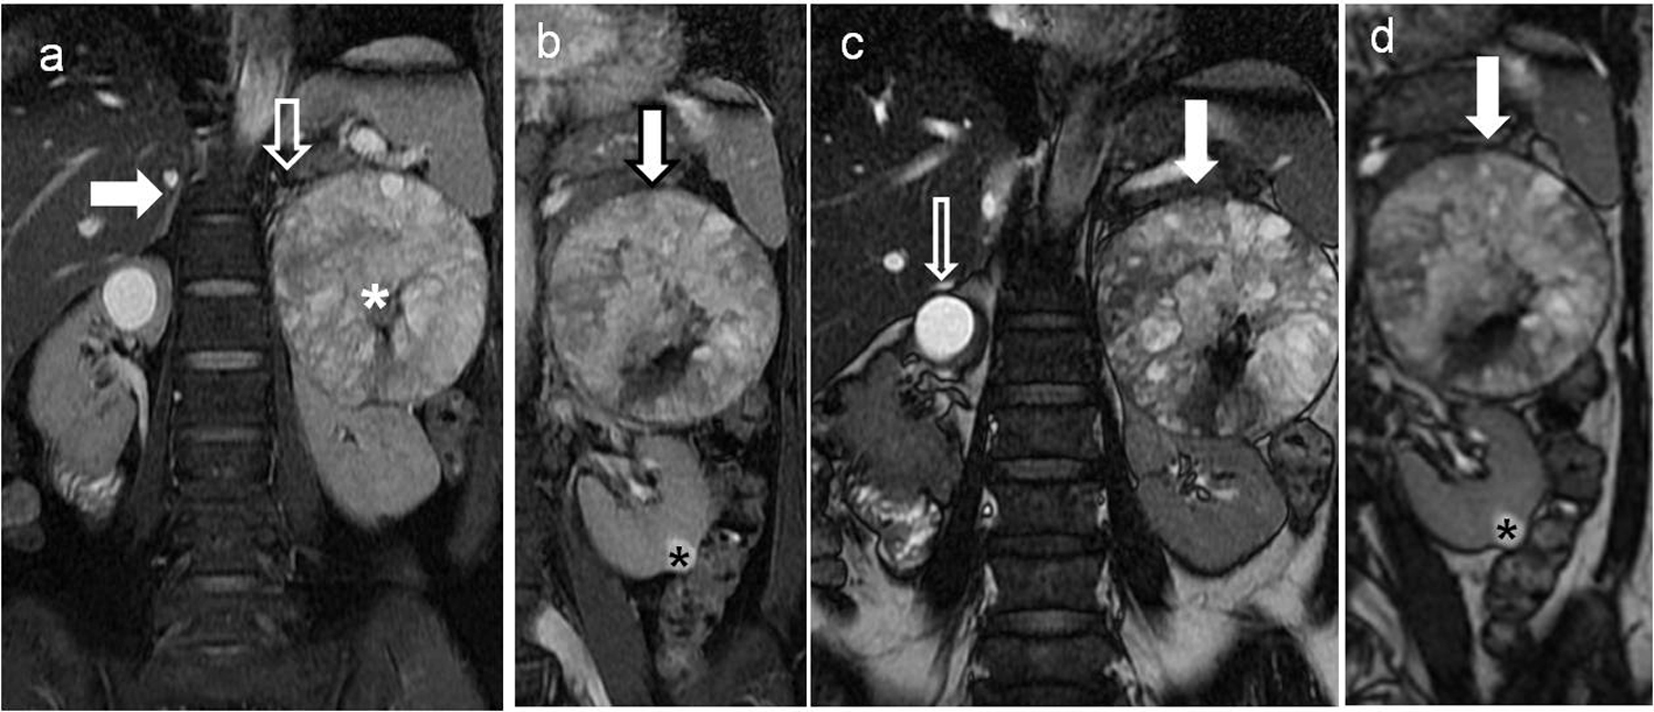

A 48-year-old lady was referred to our tertiary care institute for assessment of lump in the left flank with associated intermittent dull-aching pain since 1 month. The patient was on pain-relief medication for the same. No associated symptom of hematuria, pyuria, lithuria, recurrent urinary tract infections or fever was elicited. Co-morbidities such as diabetes, hypertension and asthma were absent. No obvious weight or appetite loss was observed. She did not give history of alcohol or substance abuse. The patient was post menopausal without prior history of surgery in the past. She did not report symptoms of profuse intermittent sweating, palpitations or fluctuations in blood pressure. Physical examination revealed a globular non-tender lump at the left renal angle and left hypochondrium. It showed a well-defined lower margin, approximately 6 cm below left costal margin on bimanual palpation and was seen to move with respiration. Laboratory investigations including urinary vanillylmandelic acid (VMA), serum cortisol and 24-h urine metanephrine levels were all within normal reference range (Table 1). MRI of abdomen, performed to investigate the lump in the left flank, showed a large soft tissue well encapsulated mass, occupying the left flank which was not identified separately from the left adrenal gland (Fig. 1a). In addition, it was noted that the tumor had a small segment of indistinct fat planes with the upper pole of the left kidney (Fig. 1b). The mass showed soft tissue heterogeneity with areas of necrosis and fibrosis appearing bright and dark, respectively, on T2WI (Fig. 1a). A small well-defined rounded lesion appearing hyperintense to the renal parenchyma was seen in the cortex of left renal mid-lower pole. Its signal was suggestive of high density contents (Fig. 1c, d). Both kidneys showed normal pelvicalyceal systems, signal intensity and parenchymal appearance on the MRI scan.

![]() Click for large image | Figure 1. Non-contrast magnetic resonance imaging (MRI) of the upper abdomen showing left retroperitoneal soft tissue heterogenous renal/adrenal mass with simple cyst in the right kidney. (a) Coronal T2-weighted fat suppressed sequence of the upper abdomen showing well visualized right adrenal gland (block white arrow) and the small partially visualized left adrenal gland (white arrow) indistinct from the soft tissue mass (white asterisk) along the left renal upper pole. (b) Coronal T2-weighted fat suppressed sequence of the upper abdomen showing soft tissue mass (bold white arrow with black outline), appearing predominantly T2 hyperintense and abutting the upper left renal pole. A small T2 hyperintense lesion in the renal cortex is also seen at the lower pole of left kidney (black asterisk). (c) Coronal FIESTA sequence of the upper abdomen showing the soft tissue mass abutting the left renal upper pole (bold white arrow). In addition, a brighter well rounded simple cortical cyst is present in the right renal upper pole (bold black and white arrow). (d) Coronal FIESTA sequence of the upper abdomen showing a relatively less bright rounded lesion in the lower pole of the left kidney (asterisk) in comparison to the cortical cyst seen in right kidney in (c). |